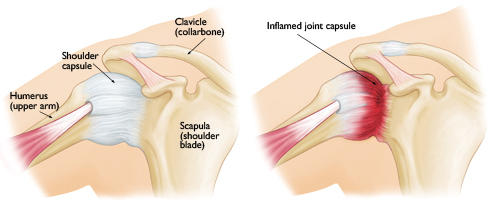

As this condition involves inflammation with subsequent thickening and scarring of the shoulder capsule (the tissue which envelopes the joint), the main problem that most patients face is stiffness of the affected shoulder. Almost all movements will be restricted and their daily activities will be disturbed bythis limitation in movement. Overhead activities (wiping the windows, combing hair, playing racket sports) will be difficult and, in the early stage, painful. The patients will also find it difficult to wash or scratch their own back, and strapping bras for ladies will be a nightmare.

In conditions where the stiffness cannot be overcome even with frequent stretching exercises, manipulation of the shoulder (where the surgeon will ‘break’ the thickened capsular tissue by forced movement under general anesthesia) is an option. Often a surgery is not needed after this procedure, unless the stiffness is persistent. In this rare instance, the surgeon will perform an arthroscopic capsular release whereby the thickened capsule is divided under direct vision (using an arthroscope – see picture below).

An arthroscopic image of the divided capsule (white tissue on the top right area) exposing the underlying muscles (red color).